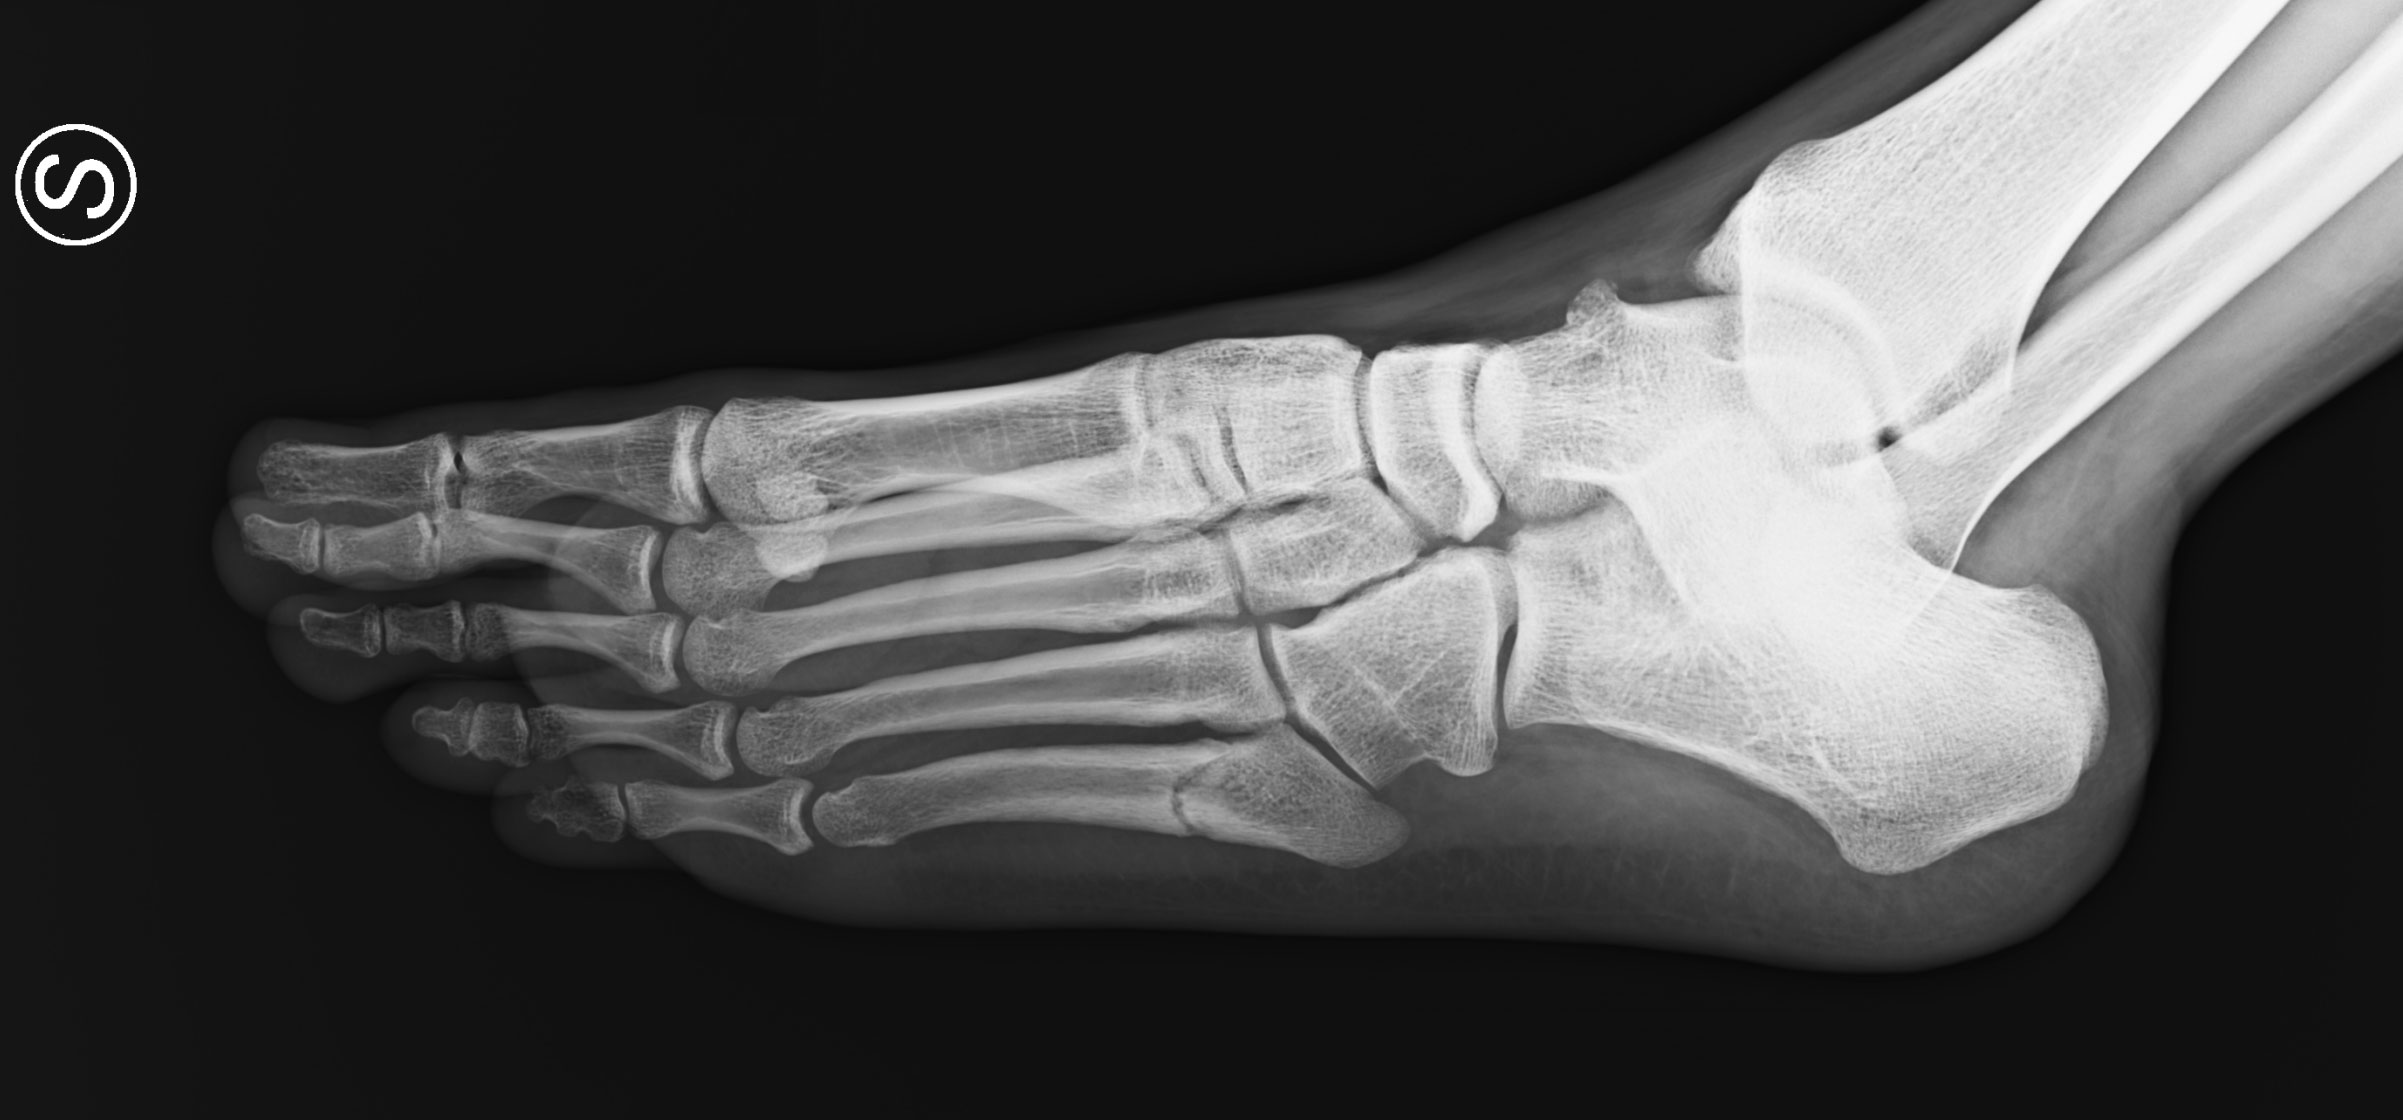

A Jones fracture affects the proximal portion of the 5th metatarsal bone, at the metaphyseal–diaphyseal junction. The injury is named after the English surgeon Sir Robert Jones, who first described it after sustaining the fracture while dancing.

The fracture typically occurs about 1.5 cm distal to the tuberosity of the 5th metatarsal. This region already has limited blood supply, and the fracture further disrupts the intramedullary arteries that nourish the bone, creating a situation of poor vascularization that slows or prevents proper healing.

Jones fractures extend toward the articulation between the 4th and 5th metatarsals. Stress fractures typically occur distal to this joint.

Diagnosis is confirmed with X-rays in anteroposterior, lateral, and oblique views. In cases of suspected stress fracture, CT or MRI may be required to detect bone marrow edema and fracture lines not visible on plain radiographs.